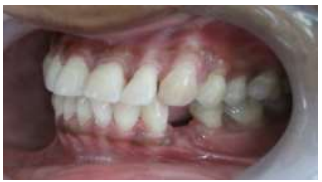

The apical opening of the pulp canal was cleaned, slightly enlarged, and sealed with resin composite. A modified ridge lap design was given to cervical area to facilitate cleaning and appearance of emerging profile. The apical portion of the root was removed to facilitate proper positioning of the tooth in an edentulous area. Intracoronal round 0.001” braided wire was inserted into the prepared tooth and bonded with composite. It was then bonded to the adjacent teeth using light cure composite. Finishing and polishing procedures were carried out using composite finishing discs and stones (Fig 02 - 05).

Figure 3 : Try in of Natural Pontic